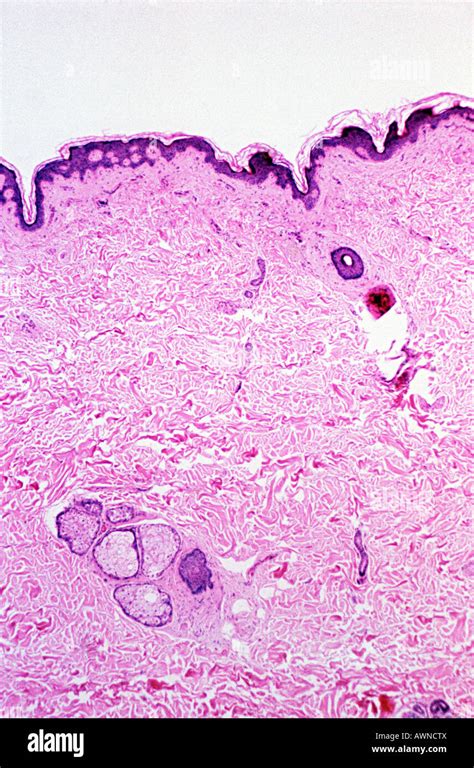

Dermatite atopica: cosa è, come si presenta, quali sono i sintomi